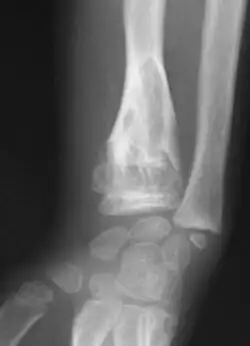

Abnormal bone growth such as shortening or thickening and deformity may be observed in patients of Ollier disease. These bone lesions are visible at birth using radiography but are usually not screened or examined for until clinical manifestations present during early childhood. However, some patients may exhibit no signs of any symptoms.[1] One study found thirteen to be the mean age of diagnosis in patients with Ollier disease. In an X-ray, there would normally be the presence of several homogeneous lesions of an oval or elongated shape with bone edges that are slightly thickened.[3] With age, these lesions may calcify and appear as diffusely minute spots or stippled. Fan-like septations or streaks would be indicative of the presence of several enchondromas. Early detection and consistent and repeated monitoring is important in order to prevent and treat any potential bone neoplasms.

-

X-ray showing enchondromas localized in the lower part of the radius of a 37-year-old patient affected with Ollier disease -